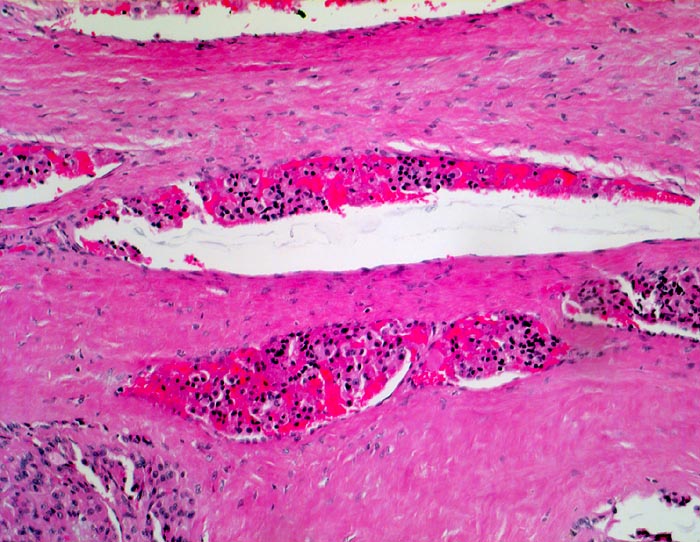

PathoPic ID 4953 - Follikuläres Schilddrüsenkarzinom: Gefässeinbruch

Follikuläres Schilddrüsenkarzinom: Gefässeinbruch

Mehrere Venen in der dicken Tumorkapsel enthalten

Tumorzellaggregate.

Vor einem Jahr Schilddrüsenteilresektion wegen follikulärem Karzinom. Jetzt Resthyreoidektomie wegen Rezidiv.

Vergrösserung

100